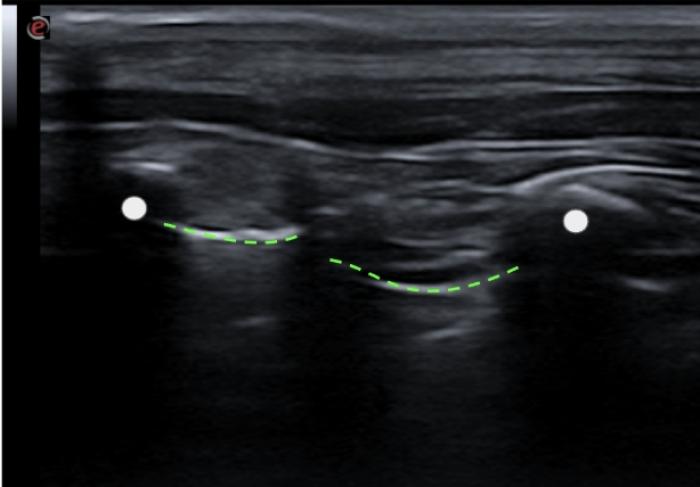

En algunas localizaciones podemos observar una pequeña discontinuidad de la LP que corresponde a las incisuras existentes entre los diferentes lóbulos, las cuales no irán acompañadas de más signos considerados patológicos, puesto que son visibles en pacientes sanos (Figura 2) (Vídeo 1).